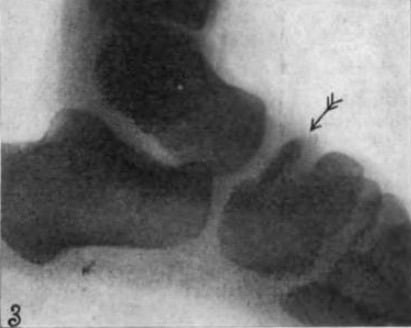

Below are images of right foot Navicular avascular necrosis (Köhler disease) in a 5 year old male

In question were young lads aged 5-9 years old. All patients complained of more or less severe pains in the region of the navicular bone. The Röntgen examination demonstrated a most peculiar finding. Everywhere the navicular bone appeared diseased, whilst all other bones of the foot presented normally. The navicular was changed in four aspects, namely its size, shape, architecture, and calcification.

The disease took its course in 2-3 years (…) healing was evident(…) not only in the clinical sense, but also in the anatomical sense, as the X-rays force us to acknowledge. The prognosis of this suffering is therefore quite favourable.